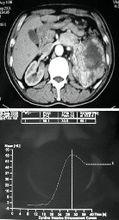

腎腫瘤組織的感興趣區域及其TDC曲線CT 灌注成像有 非去卷積法和 去卷積法,其原理是基於對比劑具有放射性同位素的彌散特點,通過從靜脈團注對比劑,在同一區域行重複快速 CT 掃描,建立動脈、組織、靜脈的時間密度曲線(TDC ),並通過不同的數學模型計算出灌注參數及彩色函式圖 ,從而對組織的灌注量及通透性作出評價。

CT灌注CBF、CBV、MTT圖西門子公司使用斜率法計算得出血容量(BV )至峰值時間(TTP )以及瞬間最大密度投影(tMIP )函式圖。BV 從組織增強峰值與動脈增強峰值的比率中計算出來。飛利浦公司 C T 灌注軟體也使用斜率法計算函式, 但使用Mullani~Gould 公式計算瞬間最大密度投影(tMIP)圖像、峰值增強圖像、TTP 、MTT 的函式圖。先在動脈內放置一個感興趣區,得到一條光滑的動脈增強曲線,以此來確定至峰值時間。G E 公司使用去卷積算法,對動態圖像數據進行分析,獲得 BF 、BV 、MTT 、PS 等灌注參數及函式圖。2001 年,該公司把多層技術與CT 灌注成像相結合研製開發了新的軟體包,實現了多層同層動態CT 灌注掃描,即“Toggling-Table”技術 ,克服了單層螺鏇 CT 的 Z軸掃描範圍小的缺點,可實現多層同時掃描,增大了檢查的縱向解剖範圍,能夠挑選病變截面較大、靜脈清楚、圖像質量好的一組進行分析,使得到的灌注參數更加準確。